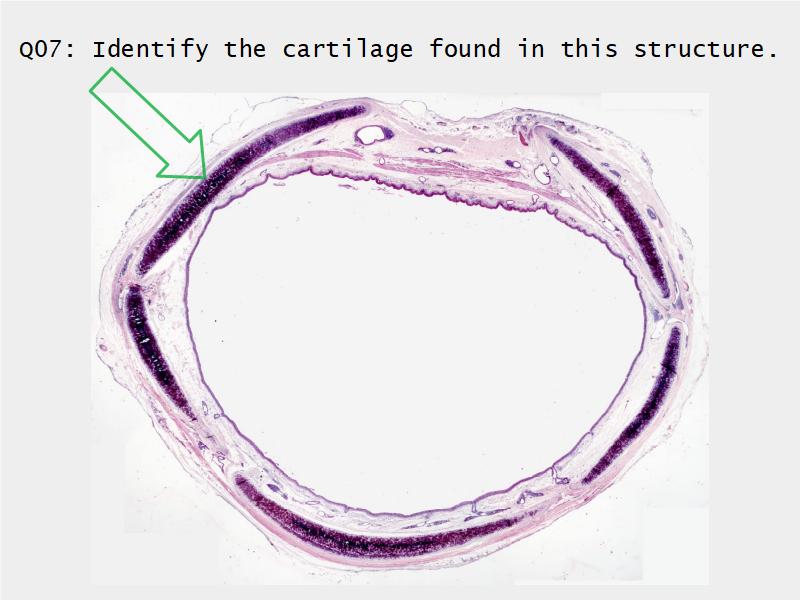

Today and Now I will do something for my future self.Trachea

- Slide 73: Trachea